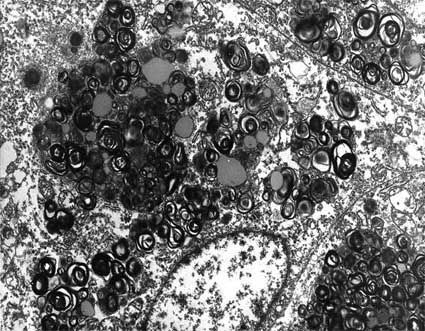

Electron Microscopy

There is osmophilic material, laminated, similar to myelin bodies; they are mainly found in podocytes, epithelium of Bowman's capsule, tubular epithelium and endothelium, although they can be seen in any type of cells. Myelin-like bodies have a periodicity of 4 to 10 nm.

Figure 15. Electron microscopy of the same case of the three previous microphotographs showing a podocyte with laminated structures in its cytoplasm: "myelin bodies". (Electron microscopy, original magnification, X4,000).

Figure 16. Another image of GSL inclusions in podocytes. (Electron microscopy, original magnification, X8,000) .

Figure 17. Inclusion in podocyte of a woman with Fabry disease and severe clinical alterations. (Electron microscopy, original magnification, X8,000).